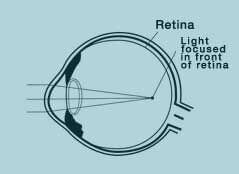

When the focal point is not completely on the retina; that is, when is behind or in front of the retina, the vision is blurred. This is called ametropia, or refractive defiency as publicly known.

Myopia (disability to look at a distance =near sightedness)

You can clearly see the objects that are close to you, but the objects at a distance are blurred.

Contrary to the spherical shape of a normal eye, your eye grows bigger in length; resulting in that the focal point of light reflected are not exactly on the retina but in front of the retina.

In that case, the correction value regarding the refraction force deficiency of your eye is showed via minus dioptre values.

When myopia increases, so do the minus values and the thickness of your eyeglasses.

In order to have a better and clearer vision, focal point has to be behind the retina. Correction via laser balancing method is obtained by means of decreasing the refractive force of cornea.